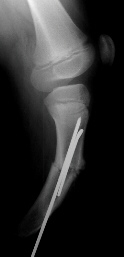

RADIOGRAPHS: Absent right fibula and lateral two rays of right foot with moderate anteromedial bowing of tibia. The right femur was also noted to be shortened.

TREATMENT: The patient initially underwent a corrective tibial osteotomy and Boyd amputation of right foot. The postoperative course was complicated by the development of a nonunion at the osteotomy site necessitating resection of the pseudarthrosis with placement of K-wires. Following this, she did well ambulating with the use of a below-knee prosthesis.